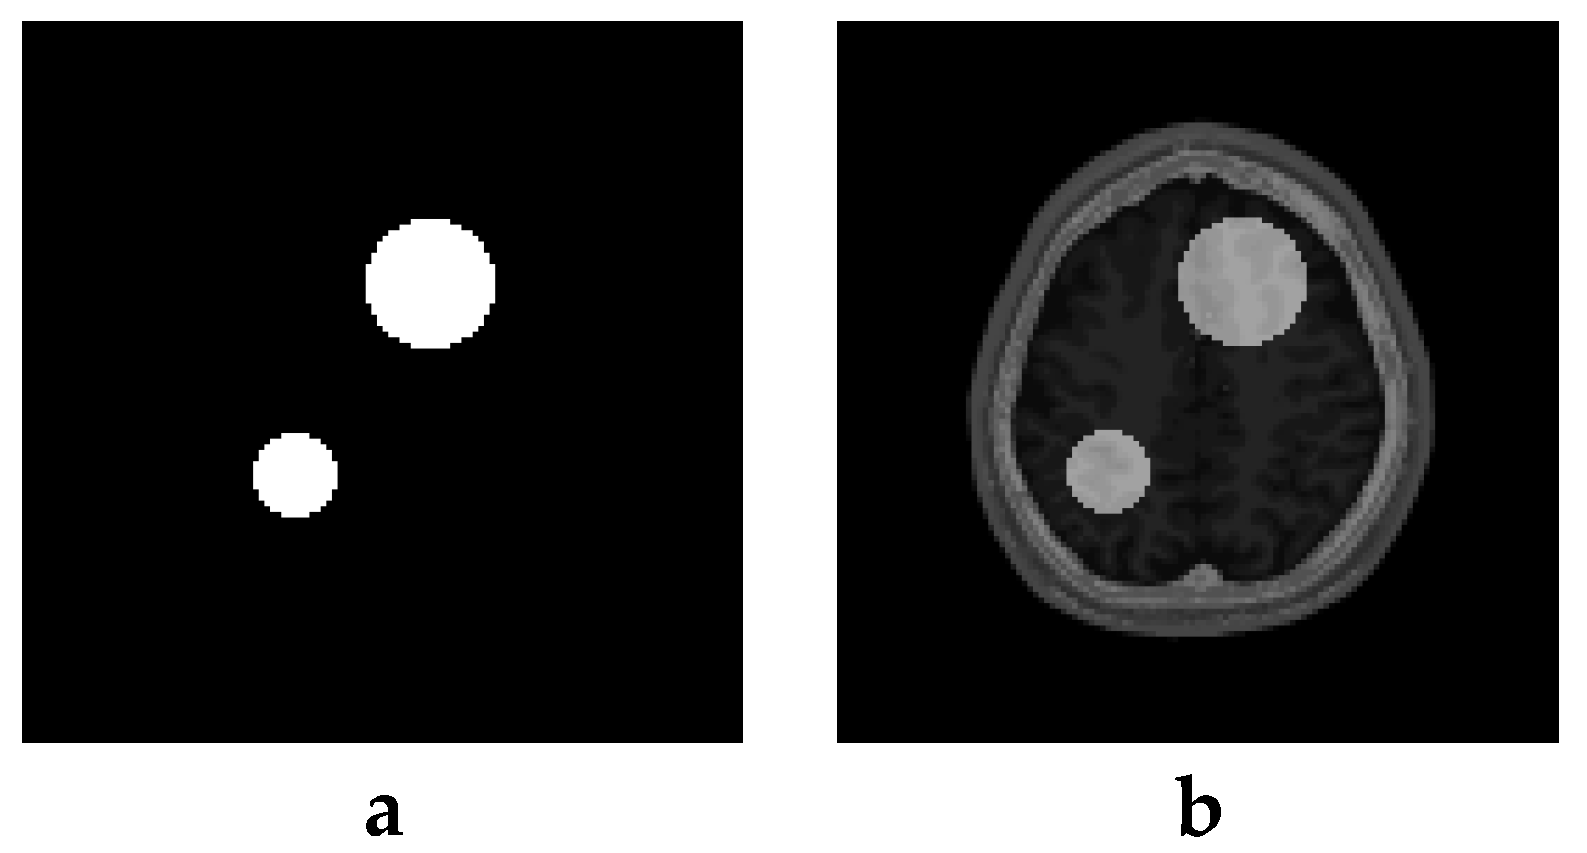

6. Creation of DSC-MRI Measurement Curves and a Brain Anatomy Model

7. Results—Exemplary DSC-MRI Study Models